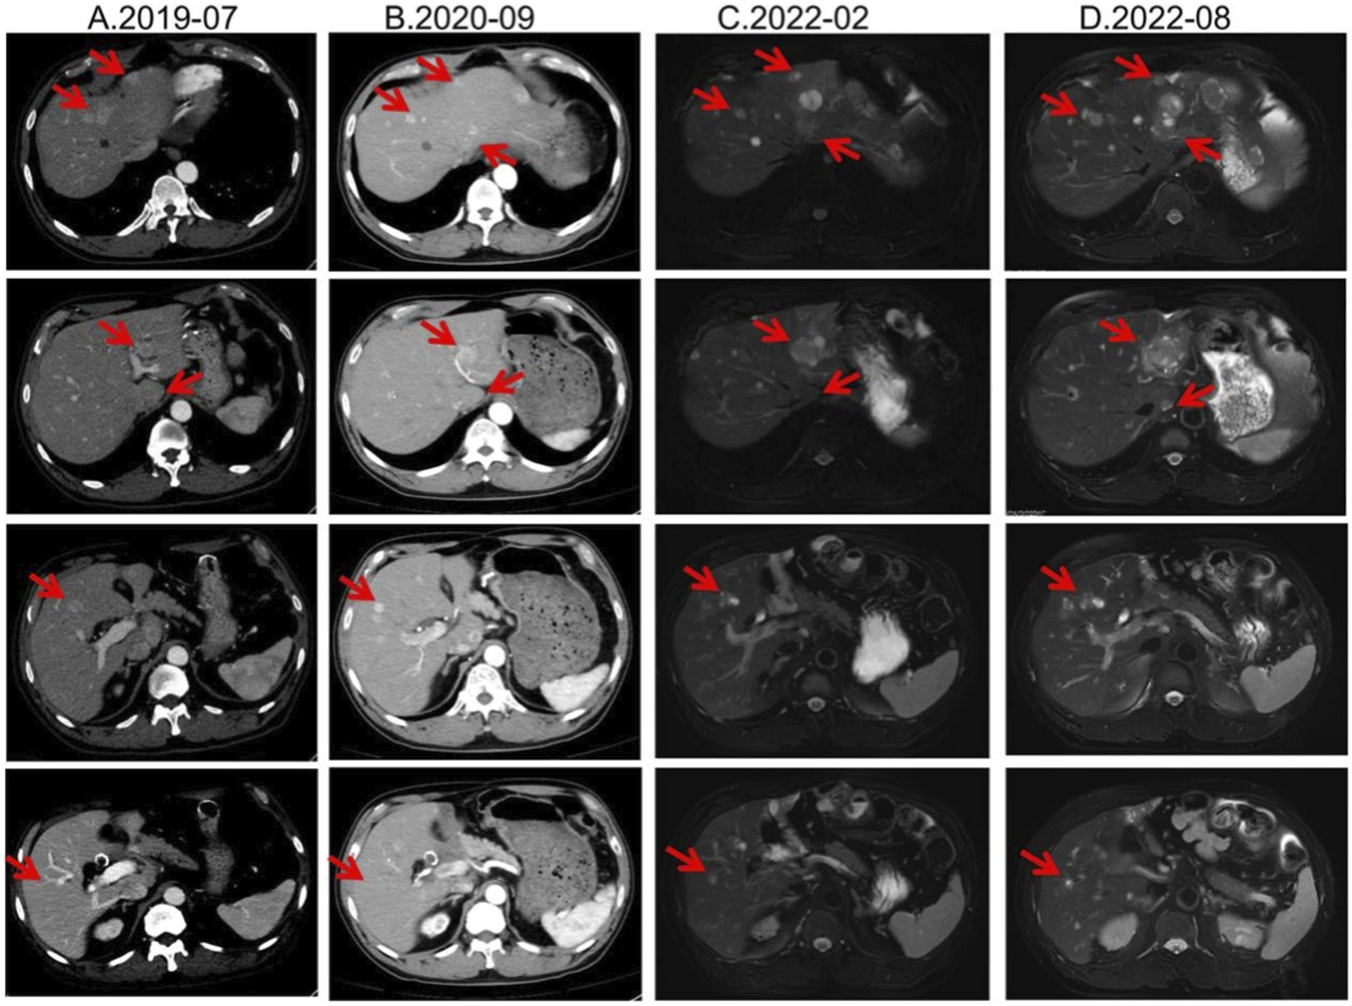

From August 2019, he received long-acting octreotide 30 mg every 4 weeks as first-line systemic therapy, combined with five sessions of transarterial chemoembolization (TACE) between 20 August 2019 and 30 October 2020. From December 2019 to February 2022, all response evaluations indicated stable disease (SD). No significant adverse events were observed; anemia improved to ∼110 g/L with iron supplementation. The August 2022 MRI showed an increased size of hepatic lesions; treatment response was assessed as progressive disease (PD), and octreotide microspheres were discontinued (Figure 1).

FIGURE 1

Lesion changes in patients treated with first-line SSA. (A) Multiple arterial-phase hyper-enhancing nodules are observed within the liver. The largest, located in the posterior-inferior segment of the right hepatic lobe, measures approximately 2.58 cm × 1.8 cm (2019-07). (B) After 15 cycles of treatment, multiple enhanced nodules were observed in the liver in the arterial phase, which were larger in the left lateral lobe of the liver, and the enhancement was reduced in the portal phase. Treatment response evaluation: SD (2020-09). (C) At the 33rd treatment cycle, the lesion in the liver showed marginal enhancement. The larger one was located in the left lateral lobe of the liver. Treatment response evaluation: SD (2022-02). (D) During the 40-cycle treatment, the lesions in the liver increased significantly compared with before. The larger ones were in the left lateral lobe of the liver, which was significantly larger than before. Treatment response evaluation: PD (2022-08).